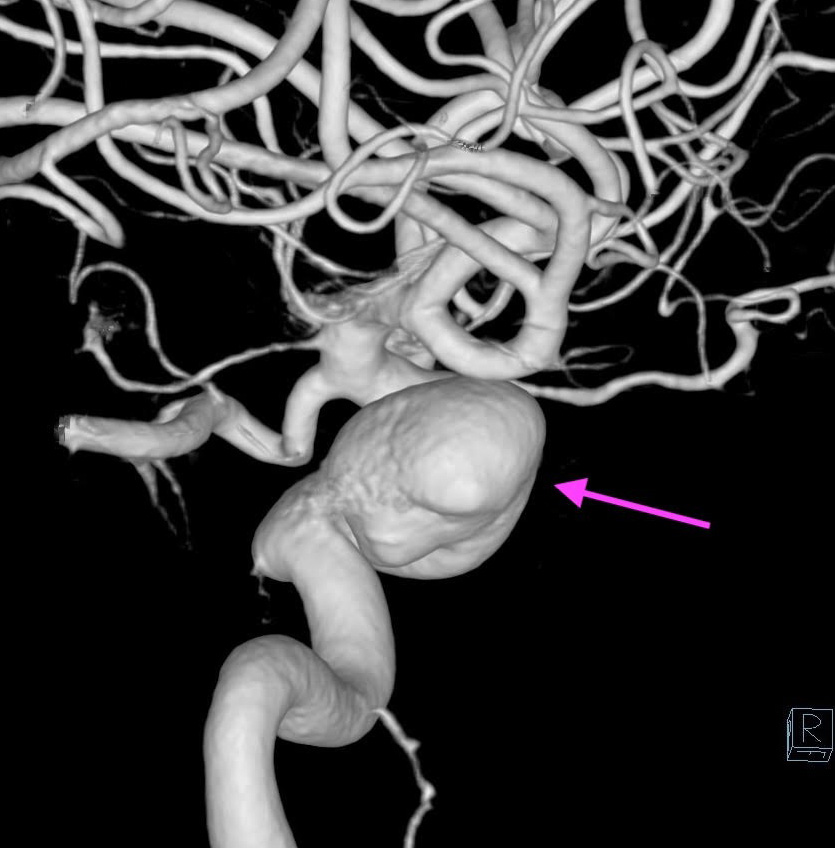

内頚動脈に大型動脈瘤を認める(矢印)